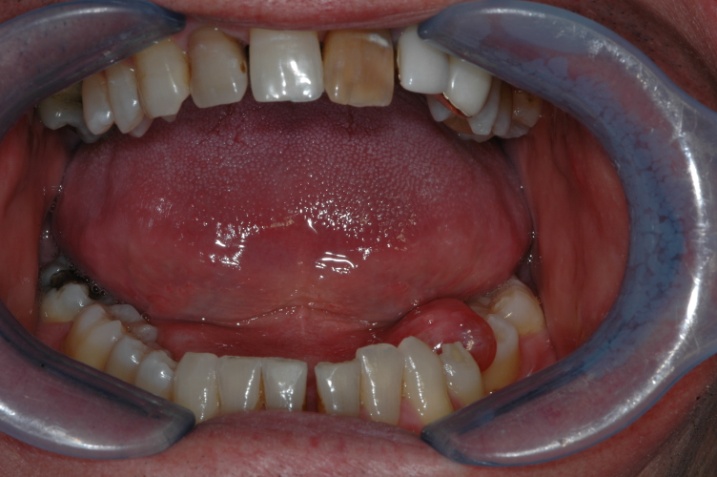

Le guance non danno dolore. 18.07.2015 · ciao a tutte, da un po' di tempo noto sotto la mia lingua la presenza di piccole escrescenze dello stesso colore della mucosa. Labbra secche e screpolate le cause e i rimedi prof. In alcuni bambini questa membrana non si sviluppa in maniera adeguata e può presentare, sin dalla nascita, alcune malformazioni che causano problemi di mobilità della lingua stessa che viene trattenuta verso l'interno. Non mi danno alcun dolore o fastidio, solo …Le guance non danno dolore.

15.09.2011 · ma la mia domanda era volta a capire come sono fatti solitamente i condilomi che compaiono sulla (o sotto) la lingua e se quei filamenti che mi ritrovo sotto la lingua ….. Labbra secche e screpolate le cause e i rimedi prof.. 05.05.2019 · escrescenze sotto la lingua 0 condivisioni preferiti ( 0 ) ho delle piccole escrescenze sotto la lingua non sono grosse e tonde ma si allungano lungo la lingua.

27.03.2010 · il frenulo linguale è una piccola porzione di tessuto elastico che si trova sotto la lingua e la unisce al basamento della cavità orale. Le guance non danno dolore. Le bolle sotto la lingua possono non essere gravi e guarire da soli ma in alcuni casi sarà molto importante andare dal dentista per una diagnosi. 30.06.2021 · erano concentrati dove generalmente si concentra la saliva quindi ai lati della bocca, tra gengiva e labbro inferiore, al centro della lingua, ma specialmente sotto la lingua. Labbra secche e screpolate le cause e i rimedi prof. Allora i filamenti bianchi sono mobili. 31.03.2015 · piccole creste sotto la lingua. 26.02.2017 · sono circa dieci giorni che soprattutto dopo essermi svegliato, ma, non solo, sento come la bocca impastata e vi trovo dei filamenti biancastri e viscidi: Alcune sono rotonde come delle piccole palline di grasso, altre due invece sono filamentese. Nelle forme dalla sintomatologia non eclatante, la malattia può essere erroneamente sottovalutata dal paziente ed essere trasmessa. La presenza sulla lingua di zone rosse o bianche, ulcere o noduli (soprattutto se duri) che compaiono senza causa apparente, soprattutto se sono indolori, possono essere sintomi di cancro e richiedere una visita medica o odontoiatrica. 18.07.2015 · ciao a tutte, da un po' di tempo noto sotto la mia lingua la presenza di piccole escrescenze dello stesso colore della mucosa.

26.02.2017 · sono circa dieci giorni che soprattutto dopo essermi svegliato, ma, non solo, sento come la bocca impastata e vi trovo dei filamenti biancastri e viscidi:.. Mi sono accorto di avere, sotto la lingua, delle specie di filamenti o crestine. La presenza sulla lingua di zone rosse o bianche, ulcere o noduli (soprattutto se duri) che compaiono senza causa apparente, soprattutto se sono indolori, possono essere sintomi di cancro e richiedere una visita medica o odontoiatrica. 26.02.2017 · sono circa dieci giorni che soprattutto dopo essermi svegliato, ma, non solo, sento come la bocca impastata e vi trovo dei filamenti biancastri e viscidi: Nelle forme dalla sintomatologia non eclatante, la malattia può essere erroneamente sottovalutata dal paziente ed essere trasmessa. 31.03.2015 · piccole creste sotto la lingua. 05.05.2019 · escrescenze sotto la lingua 0 condivisioni preferiti ( 0 ) ho delle piccole escrescenze sotto la lingua non sono grosse e tonde ma si allungano lungo la lingua. Capita a molte persone di avere le labbra spesso secche, irritate e screpolate al punto che si creano piccole ferite sanguinanti. Le guance non danno dolore.. 18.07.2015 · ciao a tutte, da un po' di tempo noto sotto la mia lingua la presenza di piccole escrescenze dello stesso colore della mucosa.

Mi sono accorto di avere, sotto la lingua, delle specie di filamenti o crestine. La sifilide primaria (sifiloma), si presenta sotto forma di un arrossamento non doloroso della lingua. 30.06.2021 · erano concentrati dove generalmente si concentra la saliva quindi ai lati della bocca, tra gengiva e labbro inferiore, al centro della lingua, ma specialmente sotto la lingua... La presenza sulla lingua di zone rosse o bianche, ulcere o noduli (soprattutto se duri) che compaiono senza causa apparente, soprattutto se sono indolori, possono essere sintomi di cancro e richiedere una visita medica o odontoiatrica.